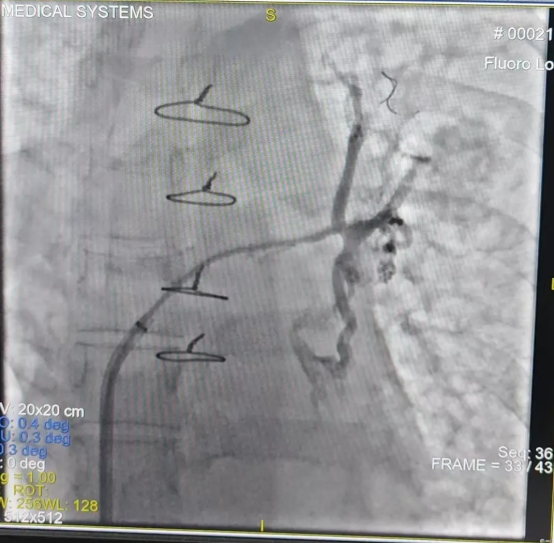

由于该手术难度极高(CMI值达17.8),心内一科与肺血管病与介入医学科联合为其制定周密手术方案。术前肺动静脉增强CT提示左肺动脉狭窄、左上、左下肺静脉闭塞,右上肺静脉狭窄。术中,心内一科尚粉青主任与孙杨医生行右心导管检查,明确其属于“毛细血管前肺动脉高压”。李积安主任、王鹏军副主任医师行经肺动脉间接肺静脉造影,再次证实左上、左下肺静脉闭塞,右上肺静脉狭窄。成功行房间隔穿刺,左肺肺静脉造影发现左上肺静脉完全闭塞,反复导丝尝试后成功开通了闭塞的肺静脉并行球囊扩张及支架植入,后再次行右肺静脉扩张,造影证实肺静脉回流正常,术后患者病情平稳,胸腔积液迅速吸收,症状明显改善,3天后胸腔积液完全消失。9月2日开学之际,李女士康复出院,终于能够回家照顾孩子,重归正常生活。

经肺动脉间接肺静脉造影:肺静脉闭塞